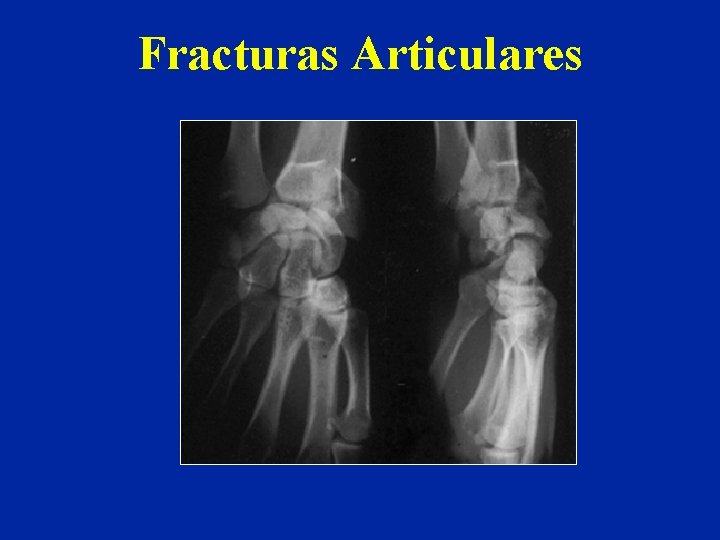

Fracturas Articulares